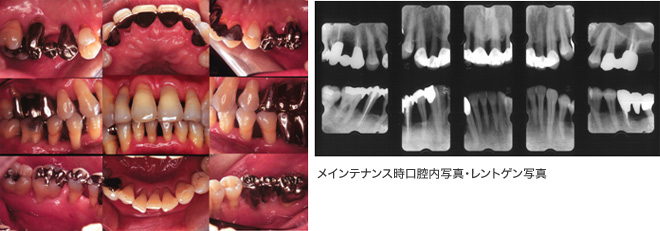

治療終了後も1ヶ月~6ヶ月に一度個々の口腔内、全身のリクスファクターとライフステージに応じたプロフェッショナルケアーとしてのバイオフィルムを取り除くメインテナンスが重要です。

松崎ファミリー歯科矯正歯科では、歯周組織再生療法と治療後のメインテナンス(プロフェッショナルケアー)を重視しています。

歯周治療を行うことによって、初診時にあった歯肉の発赤・腫脹はなくなりました。レントゲンにおいても、初診時は骨梁が不明瞭だったのが、はっきりとしてきました。治療が終了して、定期的なメインテナンスを行い始めて10年以上が経過していますが、現在でも特に大きな問題を起こすことなく良好な経過をたどっています。